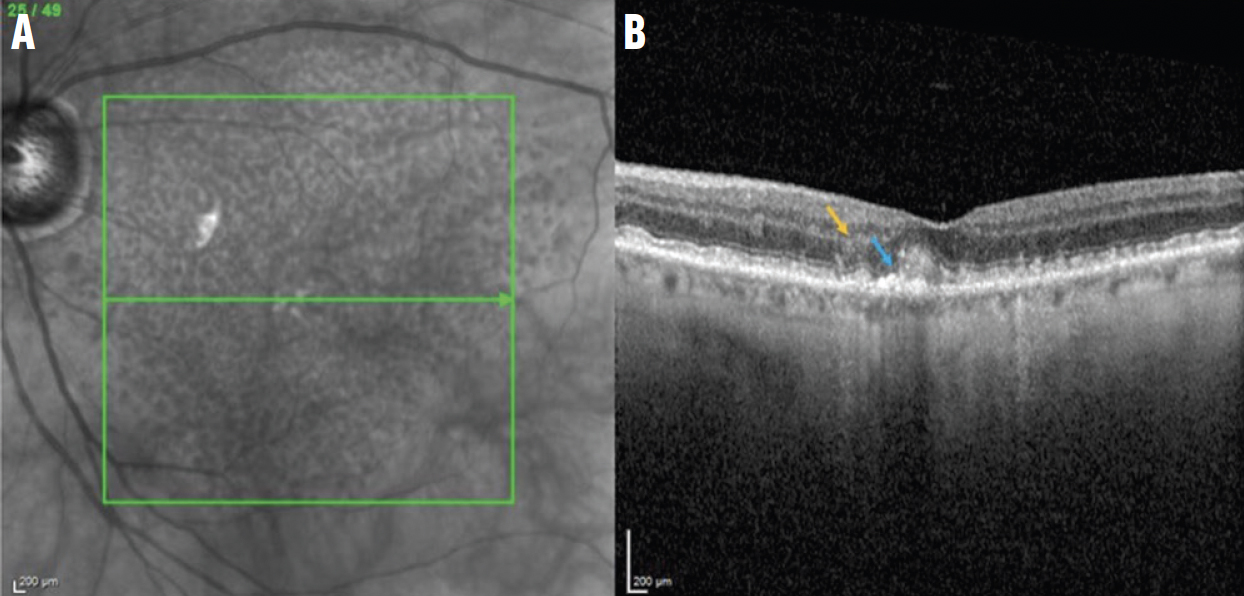

Рис. 2. NIR зображення (A) та B-скан ОКТ iRORA ураження (B) відображають порушення ELM та EZ (сині стрілки) та осідання внутрішнього ядерного шару INL (помаранчеві стрілки).